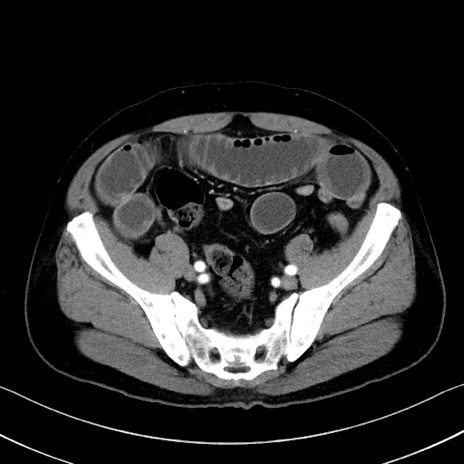

症例35(横断像)

【症例】70歳代 男性

【主訴】腹部膨満、嘔吐

【現病歴】昨日より腹部膨満感出現。本日増悪し、仙痛出現。嘔吐あり、受診。

【既往歴】糖尿病、胆摘後

【身体所見】BP 149/80mmHg、HR 74/min、BT 35.9℃、腹部:膨満、軟、圧痛なし。腸雑音減弱あり。上腹部正中切開瘢痕あり。

【データ】WBC 13500、CRP 1.72